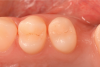

The placement of posterior restorations may lead to postoperative sensitivity.19 Two main characteristics that are important to consider when dealing with posterior restorations are the configuration factor (C-factor) of the preparation and the amount of dentin involved when compared with the amount of enamel. A preparation's C-factor refers to the ratio of bonded to unbonded surfaces. For example, Class I preparations have a C-factor of 5, and Class II preparations have a C-factor of 2. For preparations in which the amount of dentin is greater than the amount of enamel, a self-etch approach is advised because it may reduce postoperative sensitivity. Universal adhesives with functional monomers are able to chemically bond to dentin, which exists in greater amounts in posterior teeth.20 Using them in a selective enamel etching approach can improve the marginal seal that is obtained. In the clinical case described here, two premolars were restored using a universal adhesive in a selective enamel etching approach. The patient presented with primary and a secondary caries on teeth Nos. 12 and 13 (Figure 1). After isolation with a rubber dam (Figure 2), the teeth were prepared using a cylindrical bur, and the enamel was selectively etched with phosphoric acid (Figure 3). A universal adhesive was then applied, and composite was placed to restore the tooth using a cusp-by-cusp modeling approach (Figure 4 and Figure 5).

(5.) Follow-up photograph of the final restorations taken 3 months postoperatively.

Figure 5